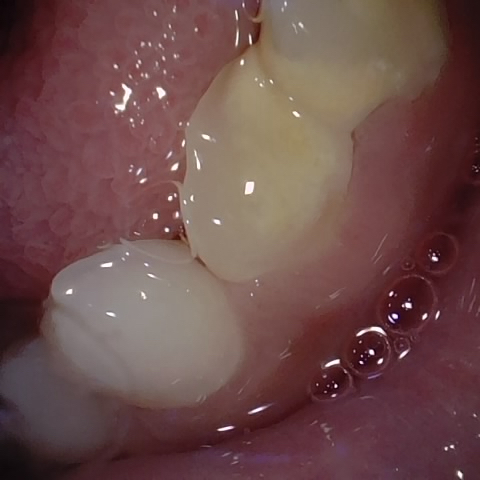

Image 214 / 680

NHD39177

Annotated as "Good"

Original Image Rendering Image